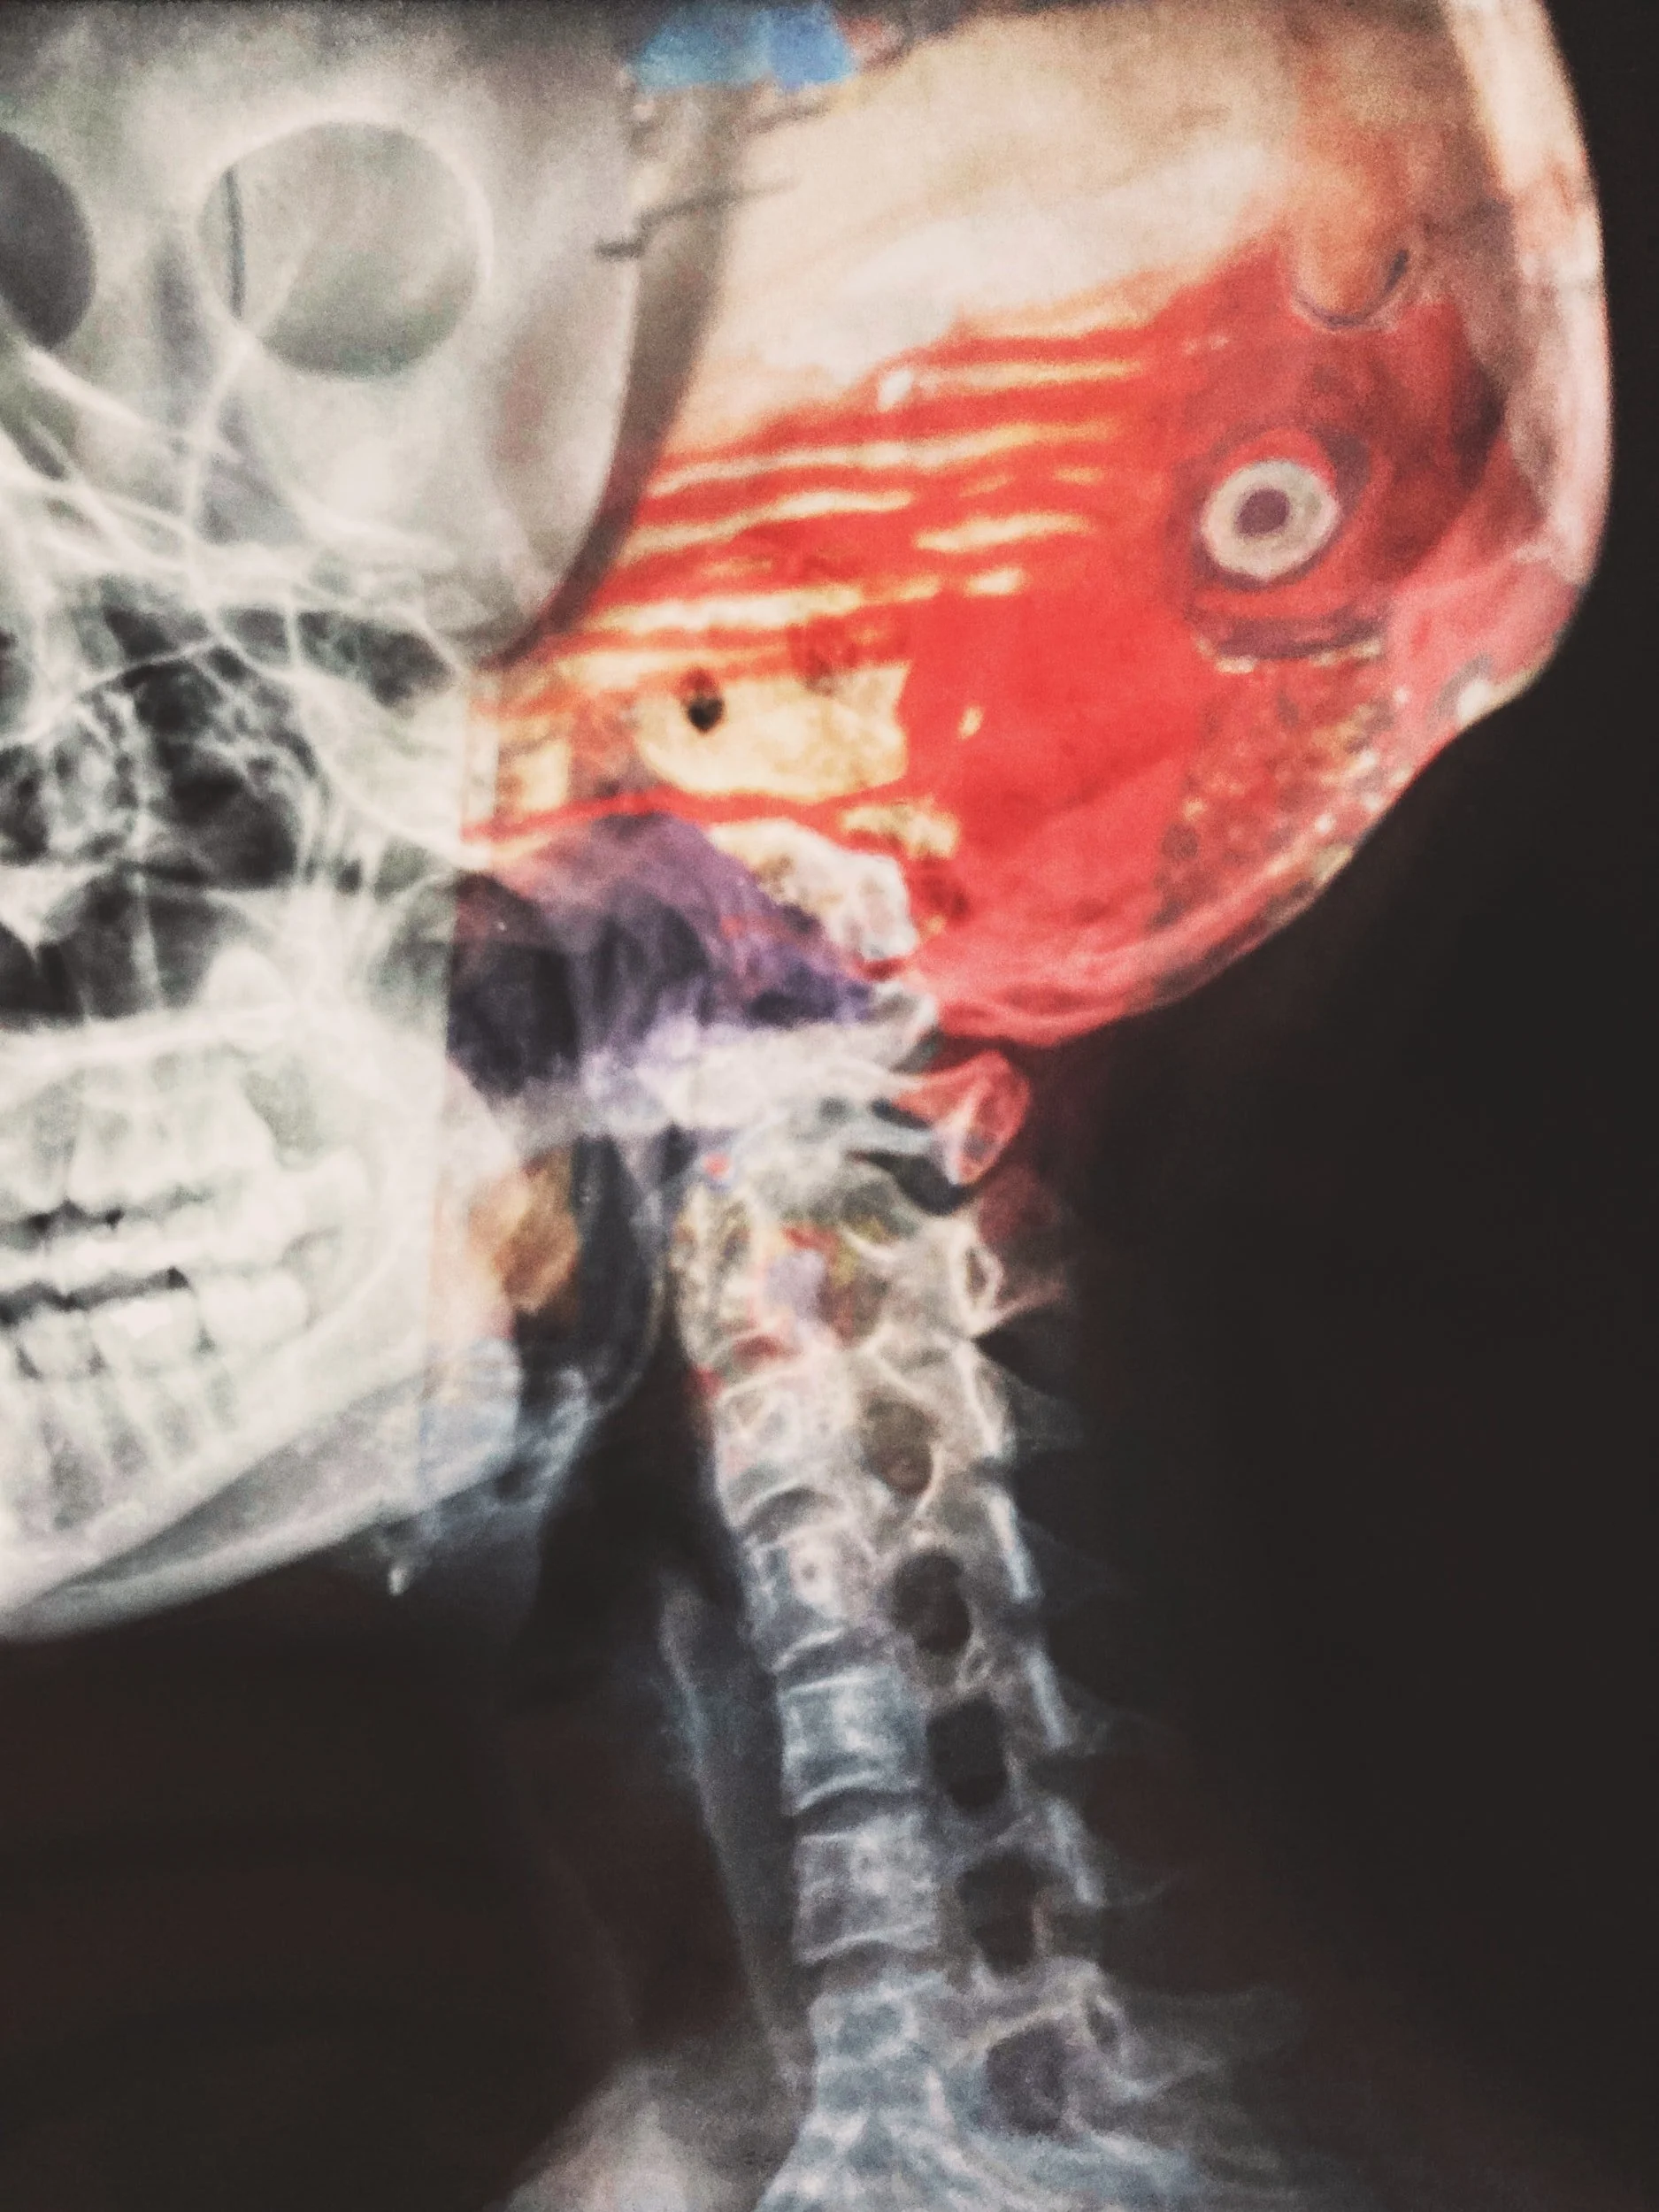

Suffering from a concussion can be extremely debilitating. However, if you know what to do, the recovery should be much smoother. Read this concussion protocol to learn how.

However, if the current news circulating NFL and brain injuries has taught us anything, it is that head trauma is nothing to be entertained by. And this form of injury affects way more people than the protagonists in films and thirty-two football teams. In fact, nearly 3 million people a year in the US suffer from a TBI (traumatic brain injury).